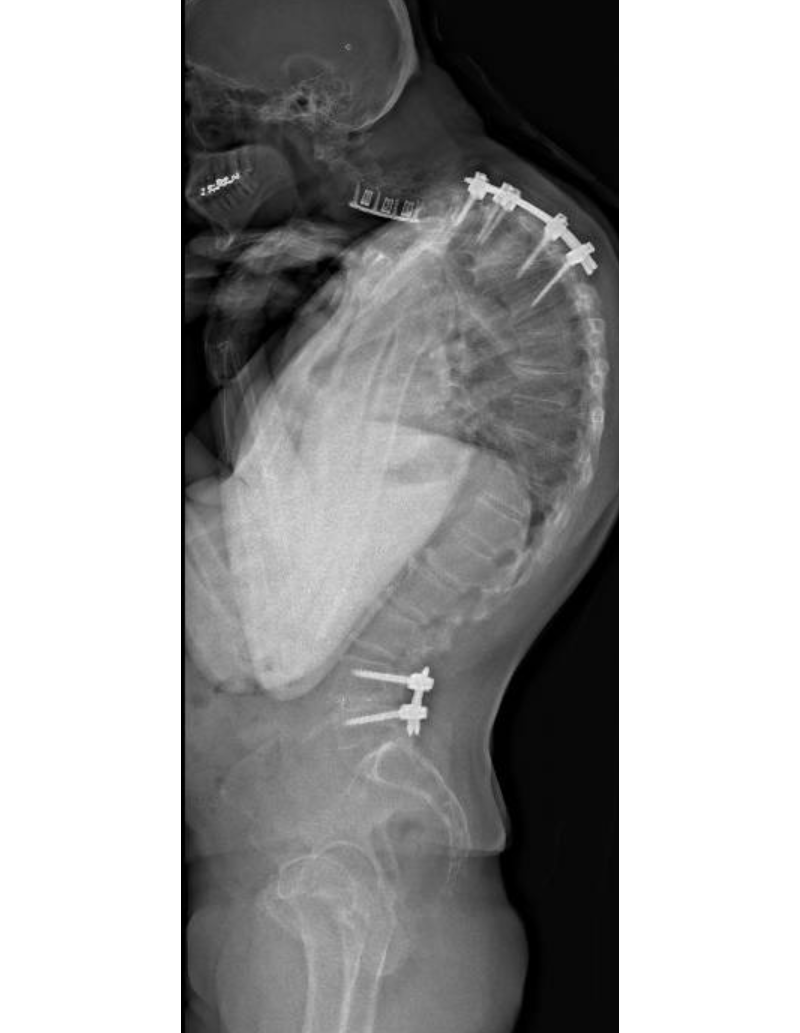

Screw and instrumentation plan of patient's spine

Frontal and lateral views of the screw and instrumentation plan created using the robotic technology